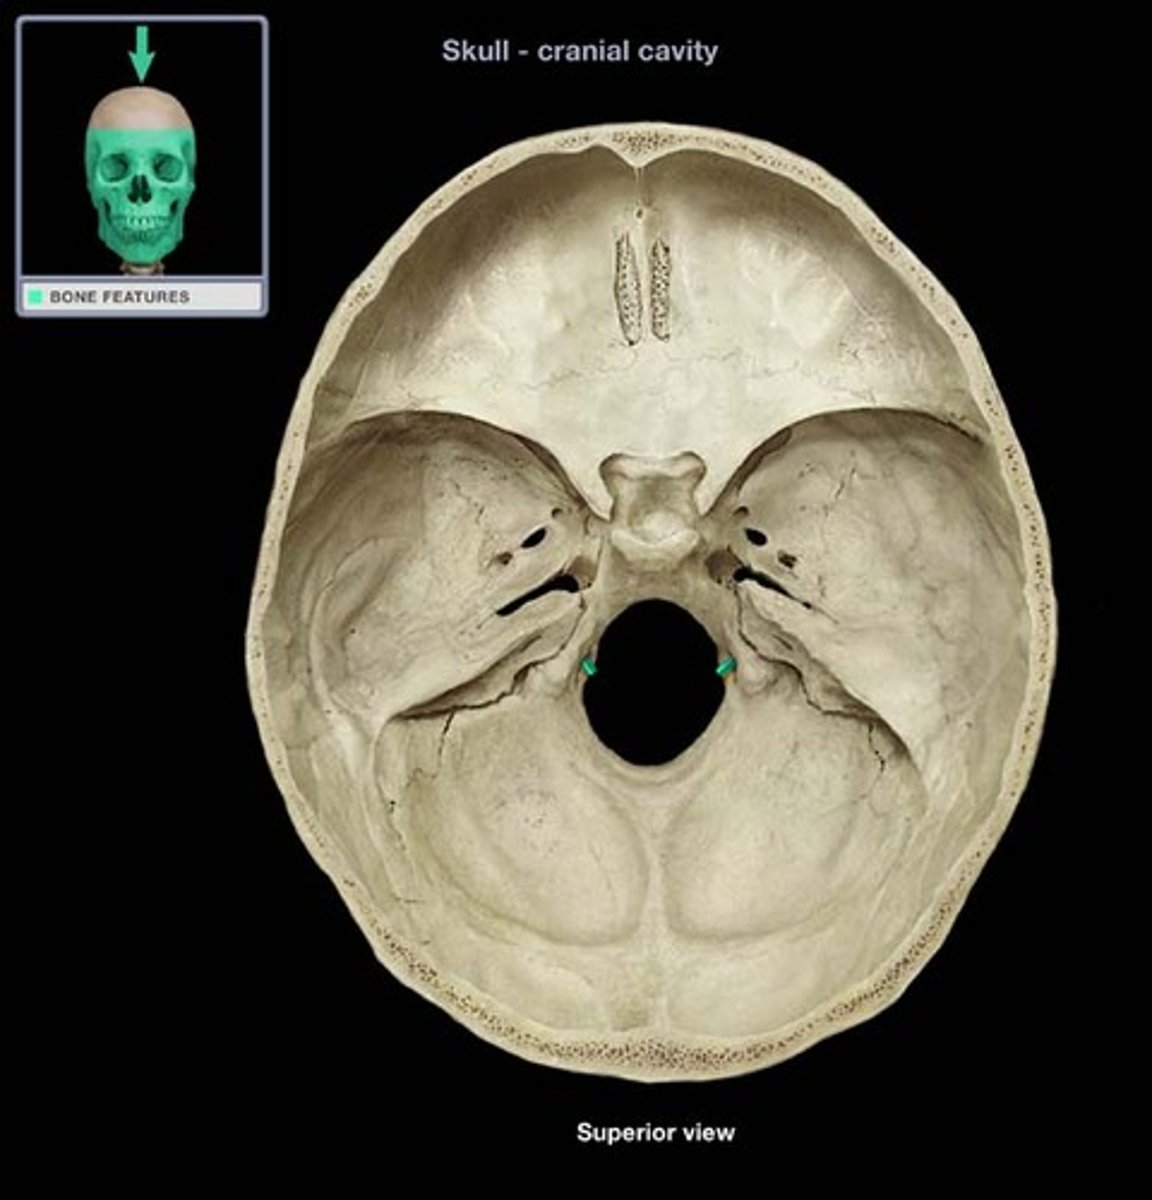

jugular foramen

opening that transmits the internal jugular vein and cranial nerves IX, X, and XI

hypoglossal canal

hole that transmits the hypoglossal nerve (CN XII)